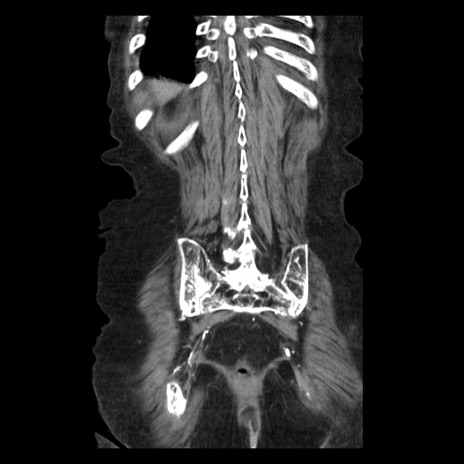

症例14(冠状断像)

【症例】 90歳代女性

【主訴】 腹痛・嘔吐

【現病歴】今朝から左側腹部痛を認めた。 経過観察していたが、嘔吐を認めたため来院。

【既往歴】 子宮癌術後

【身体所見】 意識清明、BP 127/54mmHg、P 98bpm Sp02 95%(RA)、BT 35.8°C、腹部平坦・軟腸ぜん動音聴取良好、右下腹部圧痛(+) 反跳痛なし

【データ】WBC 9800、CRP 0.46